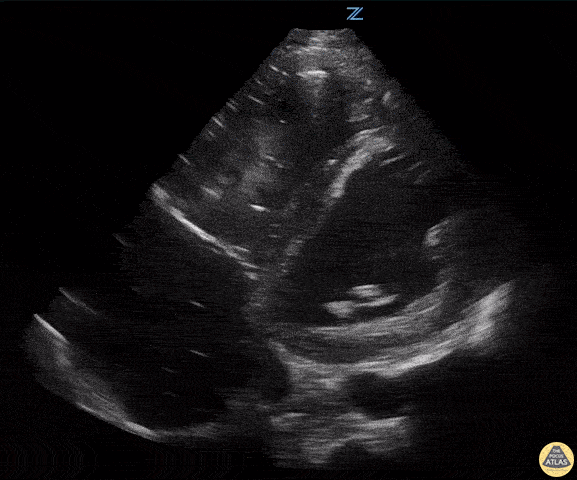

90 y/o F presents with hypotension. Patient was signed out to me by the overnight team with "sepsis" and received 30 cc/kg bolus. Patient began to have SBPs in the 70s again. She was immediately placed on vasopressors and managed for a CHF exacerbation. Image is a slightly obliqued PSAX. John Bowling, DO, Cleveland Clinic Akron General, @BModeBowling The image is slightly oblique giving the LV an oval appearance